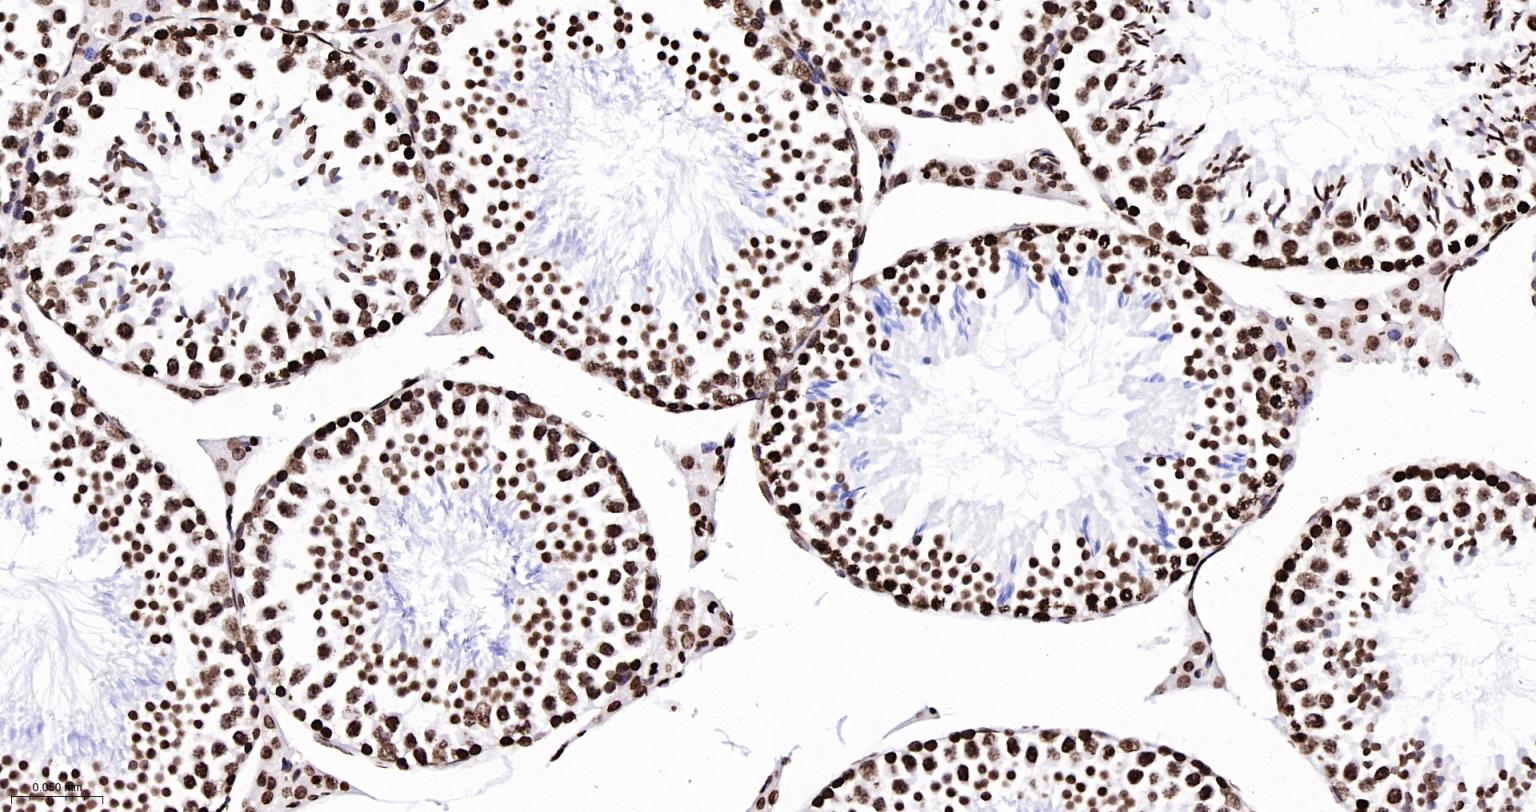

Paraformaldehyde-fixed, paraffin embedded Mouse Testicles; Antigen retrieval by boiling in sodium citrate buffer (pH6.0) for 15 min; Antibody incubation with Histone H2A.X Monoclonal Antibody, Unconjugated(bsm-61080R) at 1:200 overnight at 4°C, followed by conjugation to the SP Kit(Rabbit, SP-0023) and DAB (C-0010) staining.

Paraformaldehyde-fixed, paraffin embedded Rat Testicles; Antigen retrieval by boiling in sodium citrate buffer (pH6.0) for 15 min; Antibody incubation with Histone H2A.X Monoclonal Antibody, Unconjugated(bsm-61080R) at 1:200 overnight at 4°C, followed by conjugation to the SP Kit(Rabbit, SP-0023) and DAB (C-0010) staining.